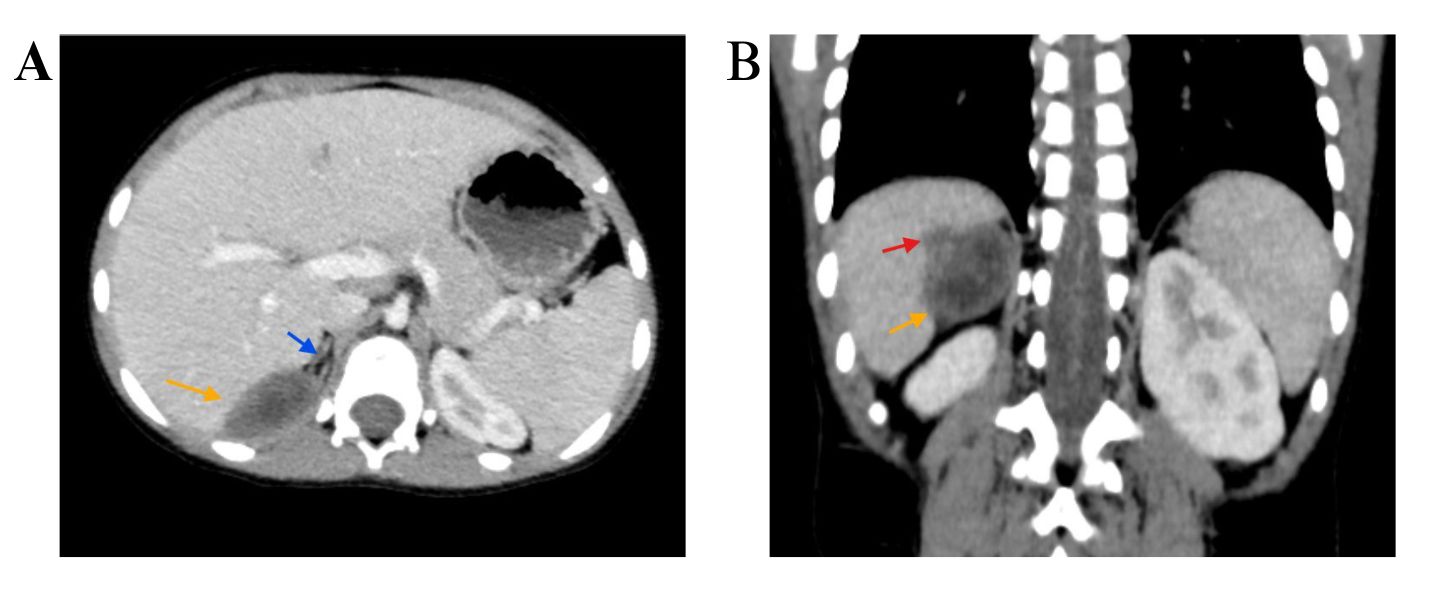

The left thyroid lobe was involved in five cases (45.5%), the right lobe in four cases (36.4%), and the isthmus in two cases (18.1%). The primary surgical approach was total thyroidectomy in seven cases (63.6%), including one patient who underwent concurrent neck dissection (Table 2). Tumor size ranged from 0.5 to 5.5 cm, with a mean size of 2.6 cm (Table 3). All the diagnoses were made post-operatively through histopathological examination (Figure 1).